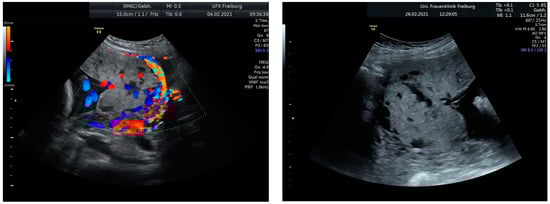

Intraoperative findings (Figure 10):

Figure 10.

depict the uterus after hysterectomy with placenta previa and increta extending to the serosa. These images show the following findings:

- The uterus following a hysterectomy illustrates the presence of placenta previa with increta extending to the outermost layer of the uterine wall (serosa).

This confirms the suspected diagnosis of placenta previa with placenta increta, which necessitated the hysterectomy procedure to manage the condition.

Histological findings:

- Uterus with mature placenta accreta et praevia totalis

- Myometrium and serosa unremarkable. Endocervical retention cysts (ventral and dorsal). Including inconspicuous membranes and a three-vessel umbilical cord

- Inconspicuous resection margins towards the cervical ventral and dorsal, towards the bladder and rectal pillars, and on the right and left parametria.